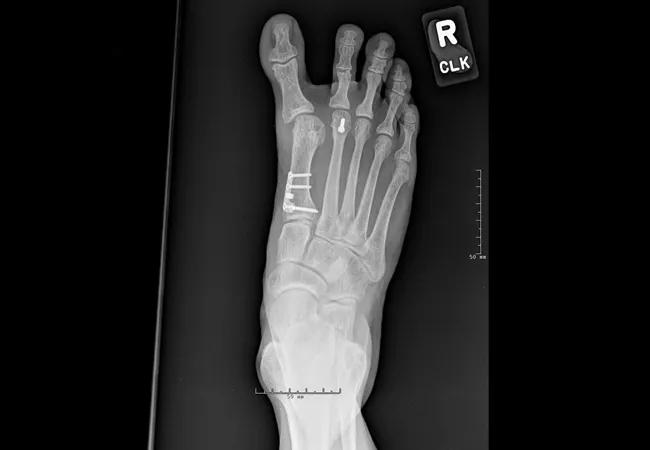

X-rays

Figures 4A-C. Radiographs of 57-year-old female with hallux varus and dorsiflexed malunion of a proximal first metatarsal osteotomy. Successful revision was achieved with first MTPJ reconstruction, correction of the malalignment, bone grafting and aggressive internal fixation.